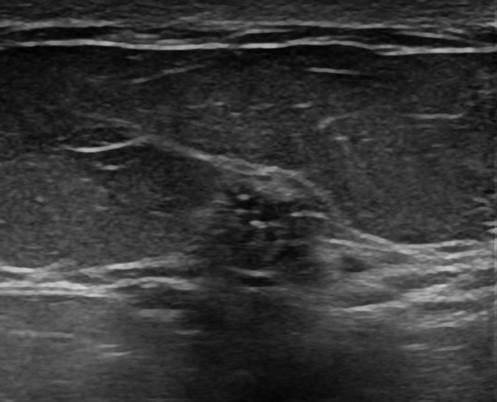

Ung thư vú

» Thông tin: Nữ giới – 42 tuổi.

» Lâm sàng: Kiểm tra sức khỏe.